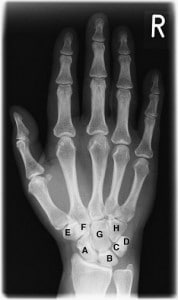

Xray_hand-178x300

Rote, trockene Augen sind keine Seltenheit und in den meisten Fällen harmlos. Gerötete Augen können aber auch ein Hinweis für fiese Krankheiten sein. Entzündliche Prozesse, wie sie bei Rheuma vorkommen, können zum Beispiel auch aufs Auge übergreifen. Genauso äußern sich auch Herpes oder Tuberkulose als roten Augen – lassen Sie im Zweifel ein gerötetes Auge also immer vom Facharzt abklären.